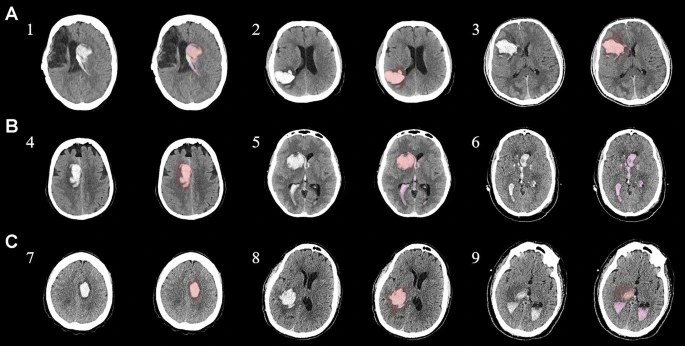

為了描述目的,患者按入組順序被賦予編號,并被連續分配到三組中的一組,每組三名。根據模型2分割,ICH體積范圍為0.1至54.9mL(平均ICH體積為23.5mL)。5名ICH患者受累于局限性腦葉,其余患者受累于基底神經(jīng)節或外囊深處。3名患者的ICH位于丘腦(圖1),1名患者的血腫位于多個(gè)腦結構(即尾狀核、殼核和蒼白球)。平均而言,MSCs是在ICH后3天注射的。

ABC/2模型1和模型2分割方法均通過(guò)線(xiàn)性回歸顯示出ICH和IVH體積的良好相關(guān)性(圖3a、b)。與模型2分割體積方法(例如每CT15-20分鐘)相比,模型1ABC/2衍生的半定量方法和改進(jìn)的Graeb IVH方法所需的時(shí)間更短(例如2-5分鐘)。有趣的是,將NIHSS評分與IVH體積M2方法進(jìn)行比較顯示出線(xiàn)性相關(guān)性(R2=0.7217),并且當IVH小于20mL或大于20mL時(shí),NIHSS評分似乎存在聚集性(圖3c)。PHE 分析顯示MSC注射劑量與PHE體積之間存在輕微的負相關(guān)關(guān)系。